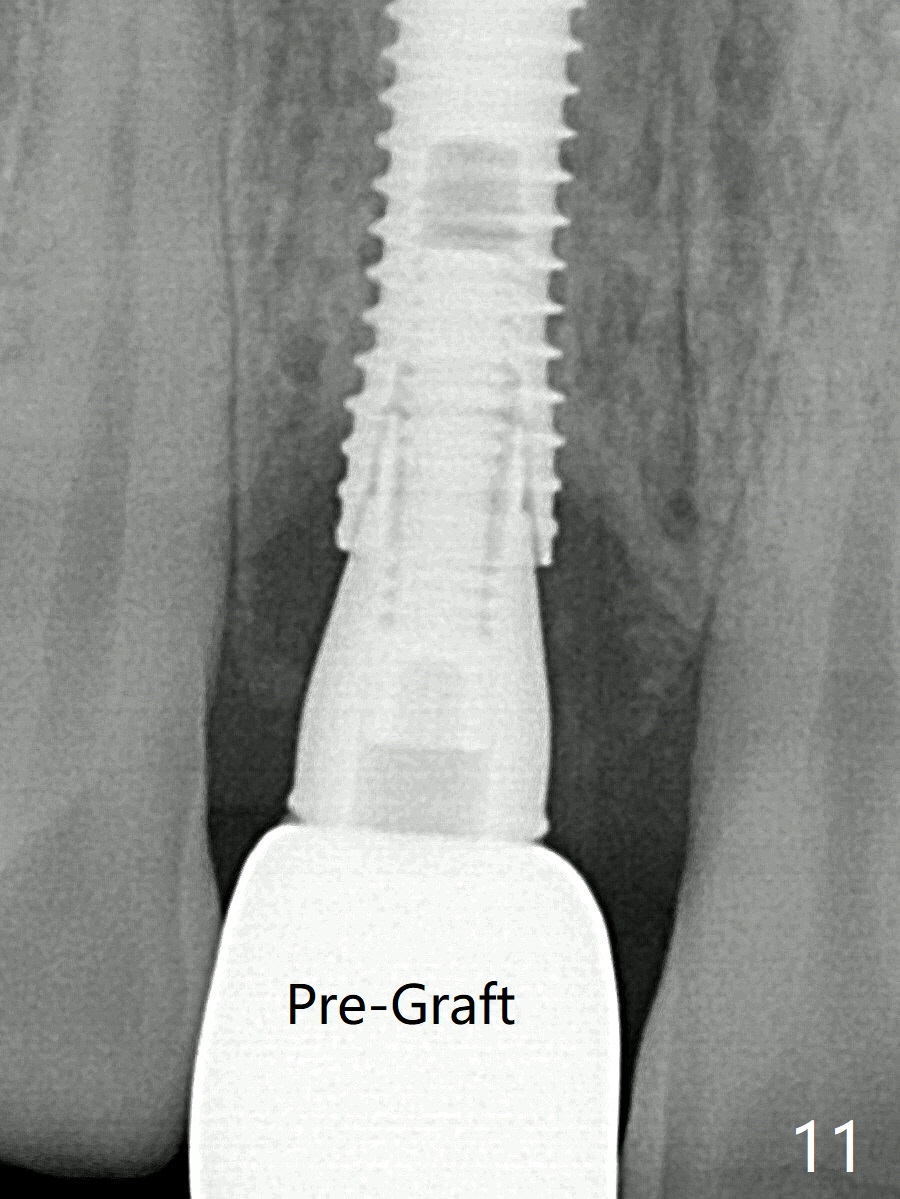

The patient returns because of purulent exudate from the buccal fistula (Fig.1 *) 1 year 9 months postop (1 year 3 months post cementation). Preop CT shows buccal thread exposure (Fig.2 arrowheads). To prevent postop gingival recession, a semilunar incision is made between the fistula and the gingival margin (Fig.3). After removal of granulation tissue (Fig.4), allograft in sticky bone form is packed (Fig.5). Following placement of PRF membrane and 6-month collagen membrane, the wound is closed (Fig.6). Since the implant (Fig.7 I) thread exposure is within bone (B) boundary (Fig.8 red dashed line), bone graft with PRF should be able to take care of periimplantitis (A: abutment). To prevent periimplantitis in similar situation, the immediate implant should be placed deep (not necessarily long, 18 mm) and narrower (3.5 mm instead of 3.8 mm). The defective buccal plate should be repaired with sticky bone and collagen membrane with incision if necessary. The wound does not dehisce 1 week postop (Fig.9) or 3 weeks postop (Fig.10, immediately post suture removal). Although bone graft seems to stay in place 6 months postop (Fig.11,12), the patient complains of bone graft expulsion sometimes. The buccal gingiva has deficiency (Fig.13). To fix it, make a remote incision (Fig.14 black line) and dissect before gingiva graft (Fig.15 dashed line). After removal of crown/abutment, the sinus track and implant surface are treated with Waterlase. A shorter cuff abutment is placed (4.5x5(4 to 3) mm) with a new provisional. The patient feels better with reduced sinus track 2 weeks postop (Fig.16).